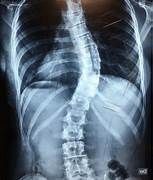

Qué es la escoliosis?

La escoliosis consiste en la pérdida de la alineación normal de la columna en el plano frontal, es decir, cuando miramos a una persona de frente. En ese plano la columna ha de ser prácticamente recta. Cuando se producen curvaturas de la columna hablamos de escoliosis.